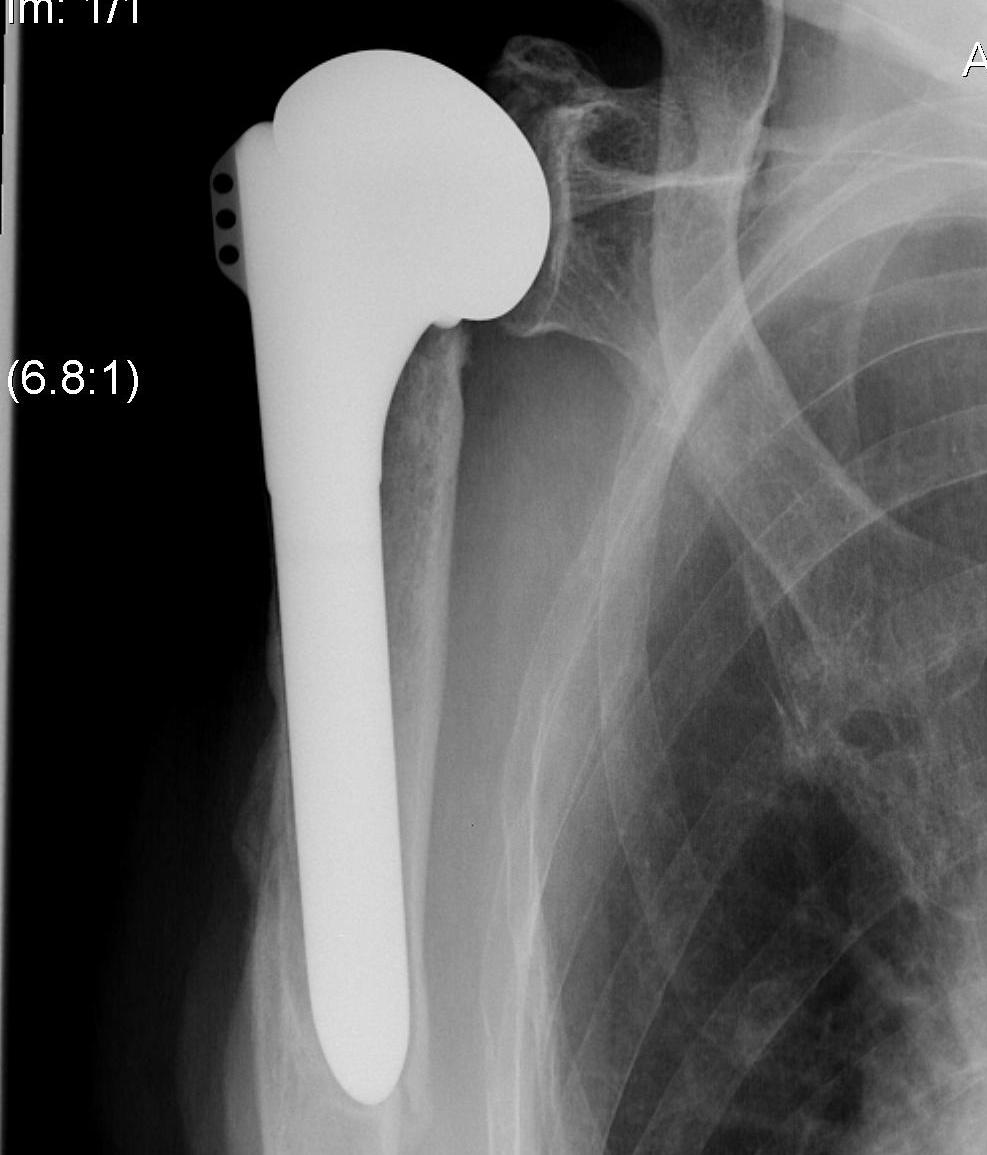

TSR Anterior Instability LateralTSR Anterior Instability AP